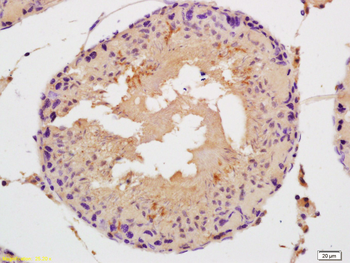

FC, IF, IHC-Fr, IHC-P

应用稀释比例:IHC-P=1:100-500, IHC-F=1:100-500, IF=1:100-500, Flow-Cyt=1ug/Test